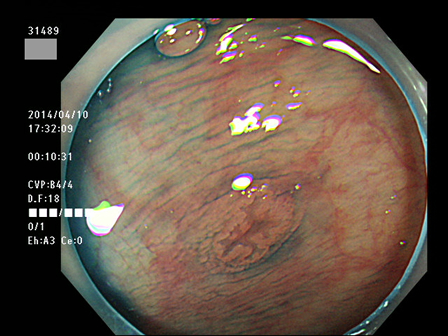

上記100名より抽出した平坦・陥凹型腺腫(=癌化の危険が高いが見落としやすい病変)の内視鏡写真